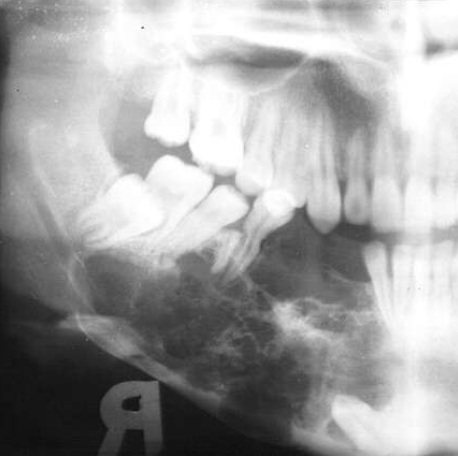

T/F: you can see B/L expansion in this radiograph

false, since this PAN is a superimposed image- you cannot tell